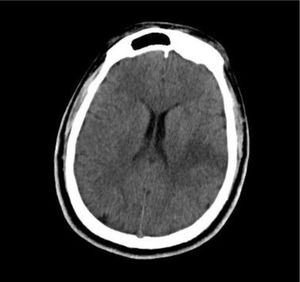

Por el déficit neurológico agudo descrito, compatible con enfermedad cerebrovascular grave, se le realizó tomografía de encéfalo, en la cual se evidenció una hipodensidad corticosubcortical en el lóbulo de ínsula, temporal posterior y tálamo izquierdos (fig. 2), por lo que se le diagnosticó infarto cerebral del territorio de ACM izquierda. Se realizó electrocardiograma, el cual mostró un ritmo sinusal sin otros hallazgos relevantes. Se decidió su hospitalización en el departamento de medicina interna para continuar con los exámenes etiológicos.